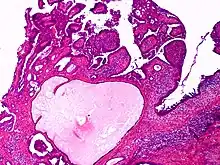

Apocrine gland carcinoma

| Apocrine gland carcinoma, papillary type | |

Apocrine gland carcinoma is a cutaneous condition characterized by skin lesions which form in the axilla or anogenital regions.[1]: 670